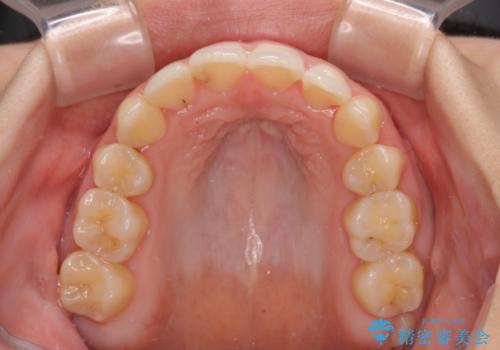

後戻りの再矯正 ワイヤー装置でデコボコと隙間を改善

詰め物で隠していた下顎前歯の隙間は、歯軸を改善することで詰め物を除去しても隙間が目立たなくなりました。

まだ改善したいところはありましたが、患者様自身は大変満足されたとのことで、治療を終えることとなりました。